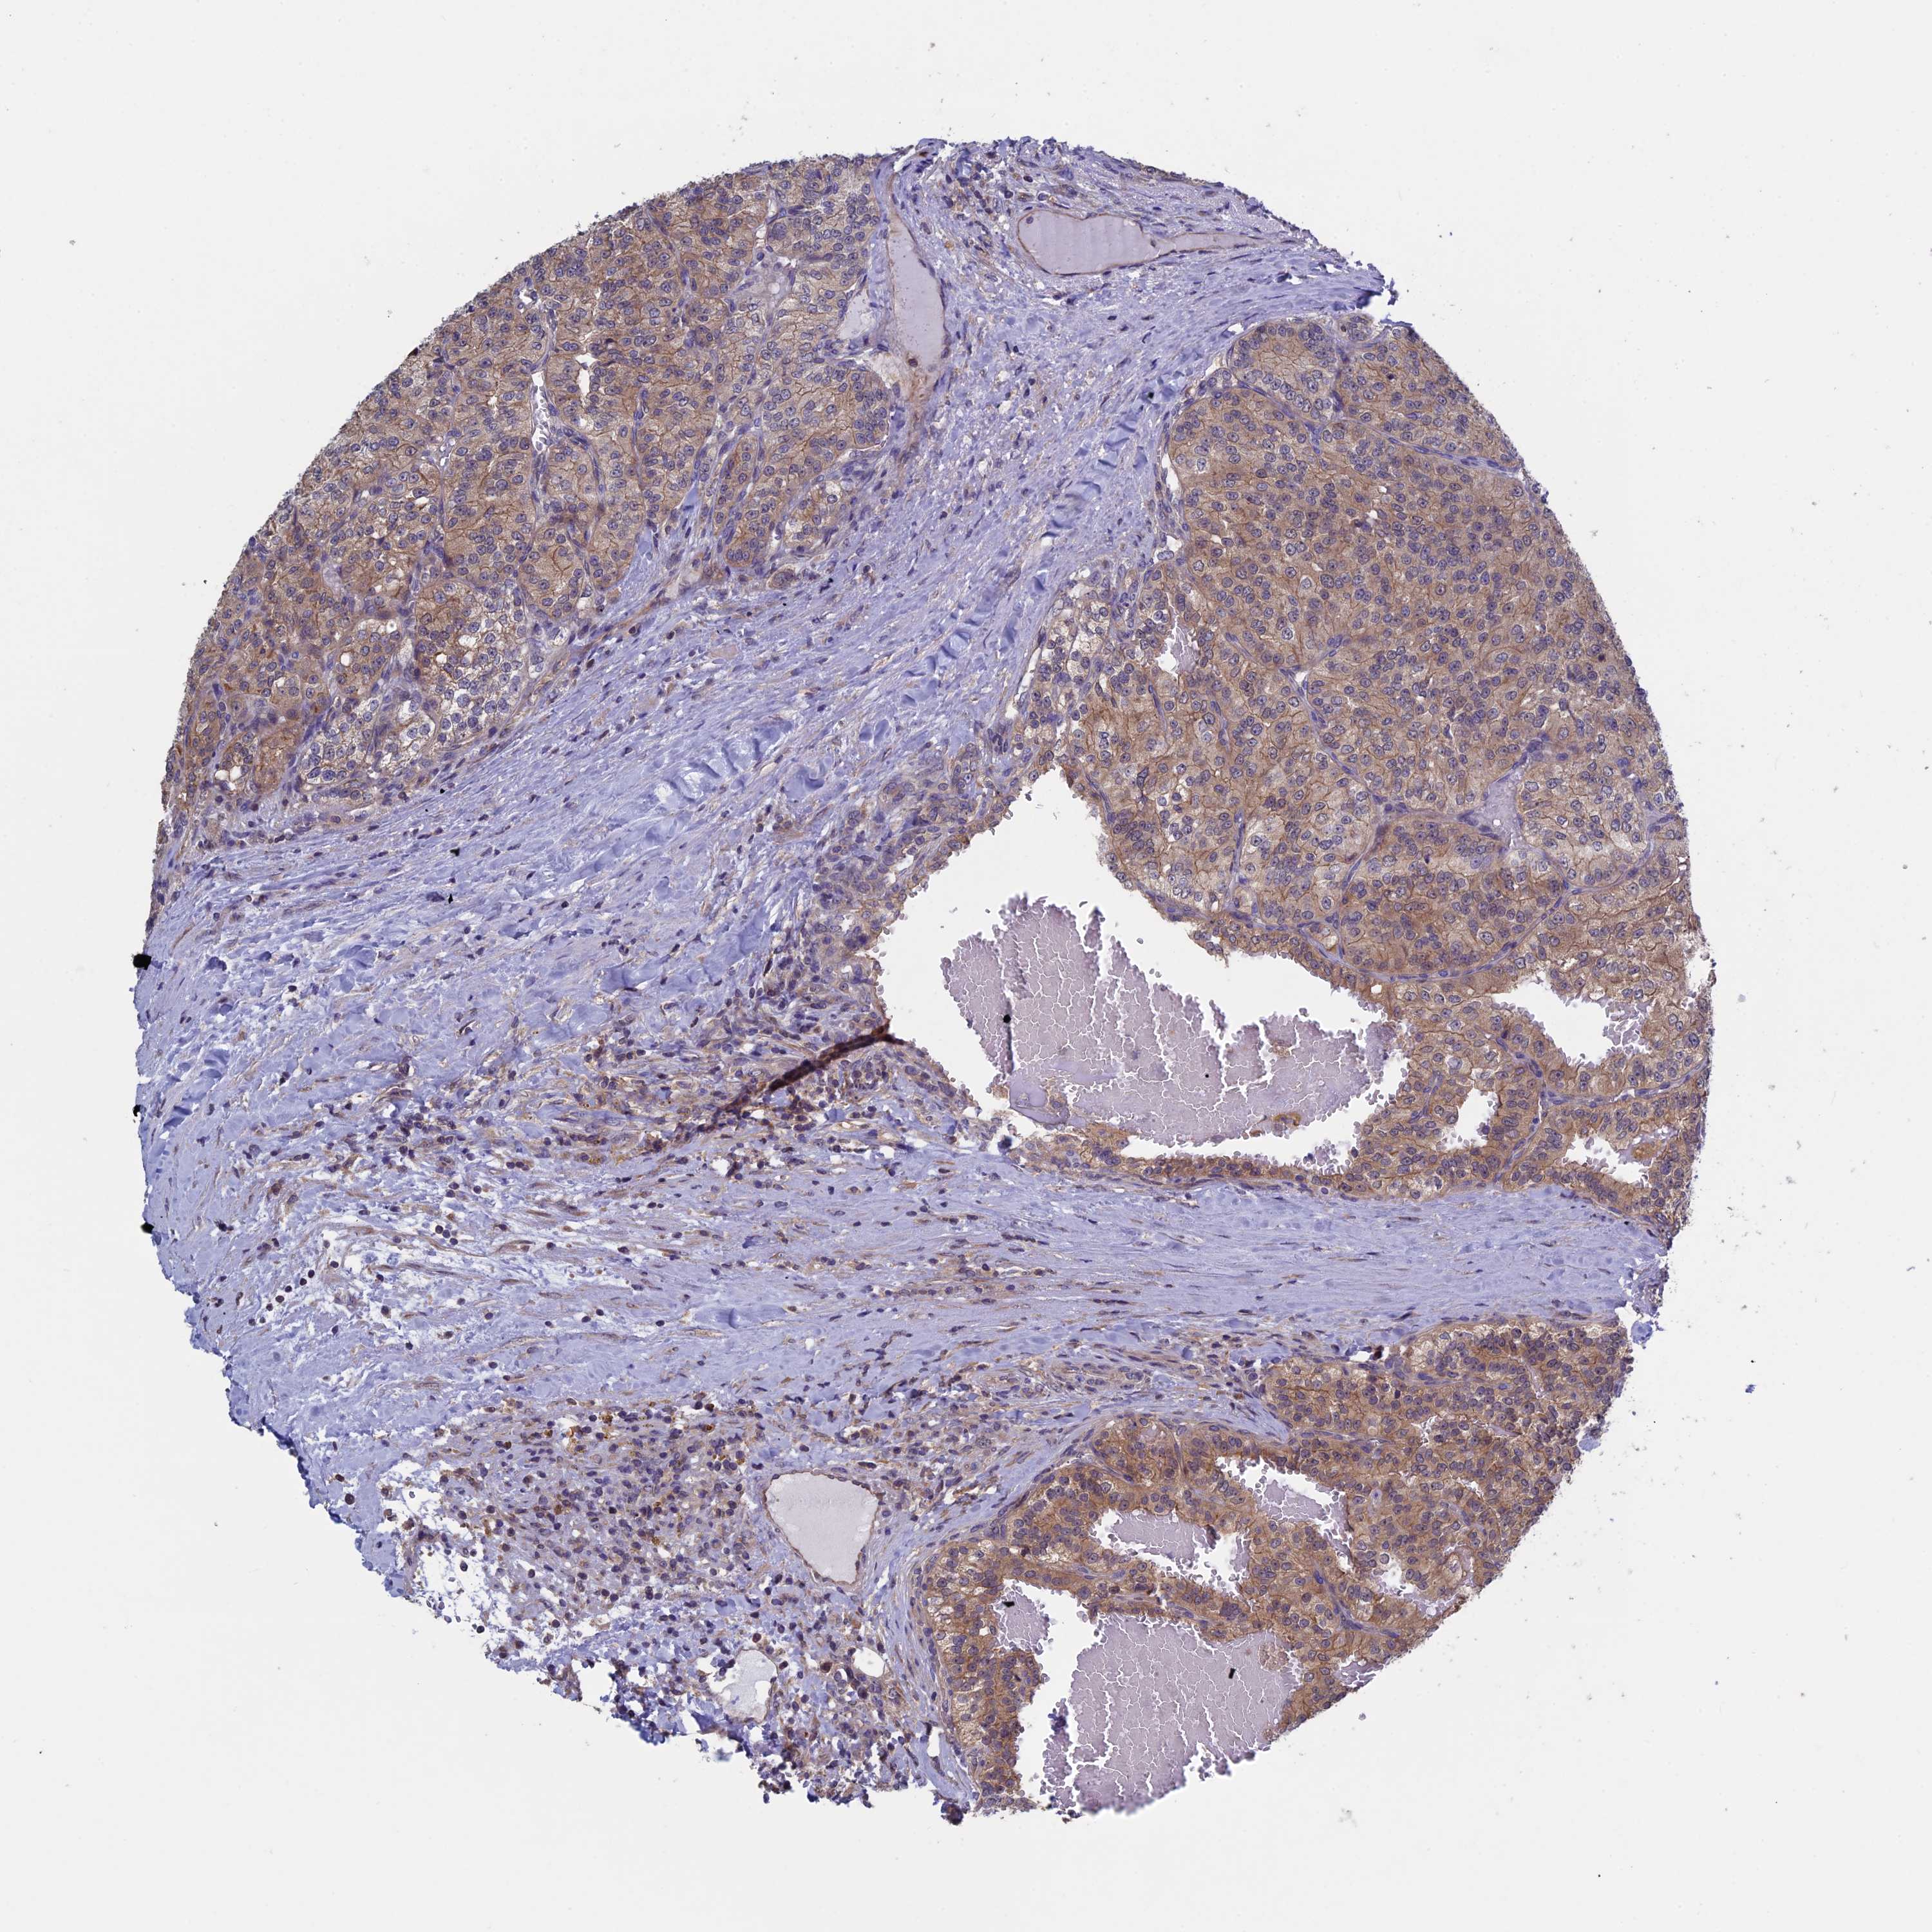

KIDNEY RENAL CLEAR CELL CARCINOMA (TCGA) - Interactive survival scatter ploti

The Survival Scatter plot shows the clinical status (i.e. dead or alive) for all individuals in the patient cohort, based on the same data that underlies the corresponding Kaplan-Meier plots. Patients that are alive at last time for follow-up are shown in blue and patients who have died during the study are shown in red.

The x-axis shows the expression levels (FPKM) of the investigated gene in the tumor tissue at the time of diagnosis. The y-axis shows the follow-up time after diagnosis (years). Both axes are complimented with kernel density curves demonstrating the data density over the axes. The top density plot shows the expression levels (FPKM) distribution among dead (red) and alive patients (blue). The right density plot shows the data density of the survived years of dead patients with high and low expression levels respectively, stratified using the cutoff indicated by the vertical dashed line through the Survival Scatter plot. This cutoff is automatically defined based on the FPKM cutoff that minimizes the p-score. The cutoff can be changed by dragging the vertical line or by entering a cutoff value in the square labeled "Current cut-off".

Under the Survival Scatter plot the p-score landscape (black curve; left axis) is shown together with dead median separation (red curve; right axis). Dead median separation is the difference in median mRNA expression between patients who have died with high and low expression, respectively. It is calculated as follows: median FPKM expression of dead patients with high expression - median FPKM expression of dead patients with low expression. This is intended to aid the user in visually exploring custom cutoffs and the associated p-scores and dead median separation.

Individual patient data is displayed and can be filtered by clicking on one or more of the category buttons on the top of the page. Categories describing expression level and patient information include: high, low, alive, dead, female, male and tumor stages. The scale of the x-axis can be toggled between linear and log-scale by clicking on the "x log" button. Mouse-over function shows TCGA ID, patient information and mRNA expression (FPKM) for each patient.

& Survival analysisi

Kaplan-Meier plots summarize results from analysis of correlation between mRNA expression level and patient survival. Patients were divided based on level of expression into one of the two groups "low" (under cut off) or "high" (over cut off). X-axis shows time for survival (years) and y-axis shows the probability of survival, where 1.0 corresponds to 100 percent.

LCMT1 is potential prognostic, high expression is favorable in Kidney Renal Clear Cell Carcinoma (TCGA)

Best expression cut offi

Based on the FPKM value of each gene, patients were classified into two groups and association between prognosis (survival) and gene expression (FPKM) was examined. The best expression cut-off refers the FPKM value that yields maximal difference with regard to survival between the two groups at the lowest log-rank P-value. Best expression cut-off was selected based on survival analysis .

When clicking on this number, the vertical dashed line indicating cut-off, the interactive survival plot, and the Kaplan-Meier curve will be adjusted to show results based on the best expression cut-off.

: 29.02

TCGA RNA samplesi

RNA-seq data is reported as average FPKM (number Fragments Per Kilobase of exon per Million reads), generated by the The Cancer Genome Atlas (TCGA) .

Normal distribution across the dataset is visualized with box plots, shown as median and 25th and 75th percentiles. Points are displayed as outliers if they are above or below 1.5 times the interquartile range. FPKM values of the individual samples are presented next to the box plot.

Average pTPM 29.0

Number of samples 521